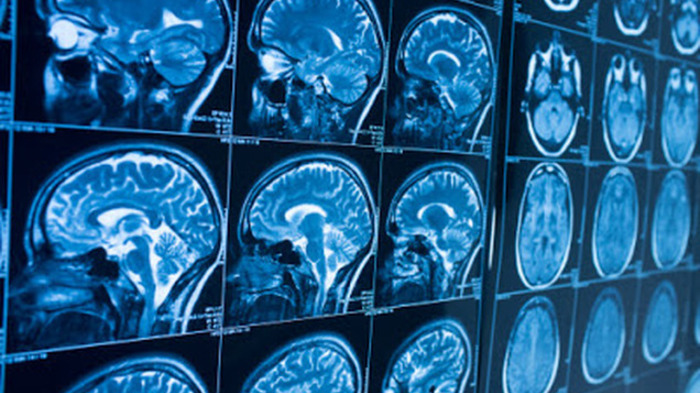

It's hard to fathom how our subjective lives can be rooted in the spongy flesh of brain matter. Yet the reality of the brain-mind link was made stark half way through the last century by the Canadian neurosurgeon Wilder Penfield. Before conducting neurosurgery on epilepsy patients he stimulated parts of their brains directly with an electrode, triggering in them subjective sensations that varied according to the source of stimulation.

In a new case study, a team of Swiss and French neurologists followed a similar strategy during brain surgery with a 23-year-old female patient. She has temporal lobe epilepsy and experiences "ecstatic auras" before seizure onset. During these periods she has "intense feelings of bliss and well-being", a floating sensation in her stomach, enhanced senses and time appears to contract.